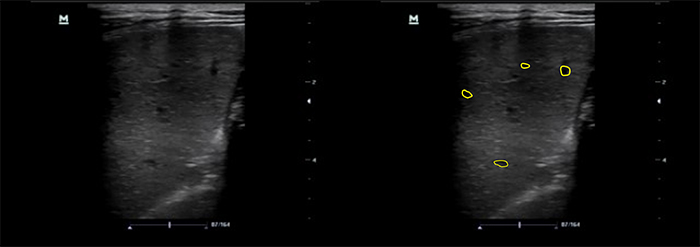

- Splenic micro abscesses: OR 1.921 (Figures 7 and 8, Videos 9 and 10)

- Micro abscesses will appear as small hypoechoic lesions. As they become numerous, they can coalesce and enlarge.

Figure 9. Spleen with microabscesses using linear transducer

Figure 10. Spleen with high frequency linear transducer, A- microabscesses and granulomatous infiltration, B- normal spleen echotexture

- The use of a high frequency linear transducer can improve your ability to identify splenic micro abscesses. 21,26-8 Freezing the image and scrolling manually can slow the image down enough to identify small micro abscesses (Figure 8).